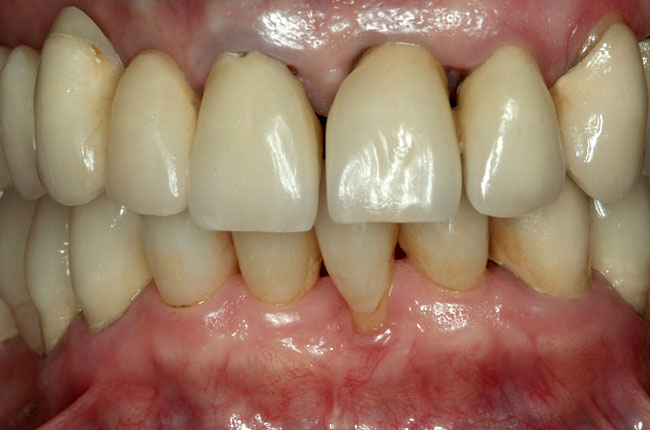

Abb. 2

Abbildungen 3-5: Die klinischen Fotographien zeigen den Zustand nach der ersten professionellen Zahnreinigung.